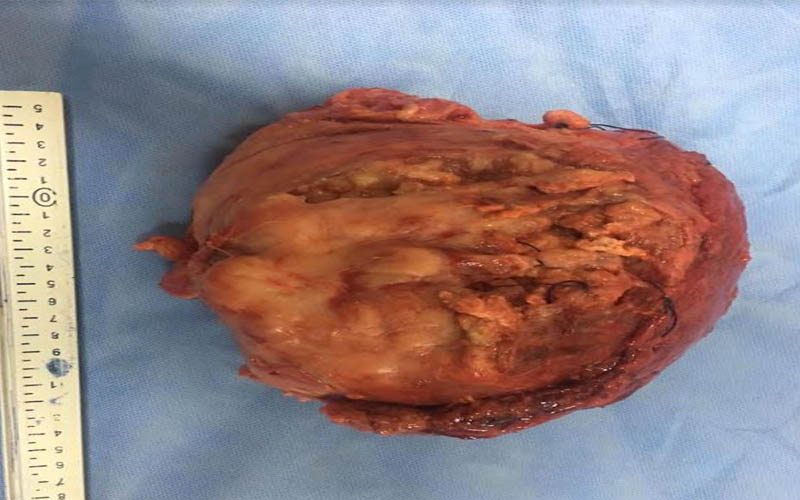

أعلن الدكتور هشام مختار حمودة رئيس قسم جراحة المسالك البولية والكلى بجامعة أسيوط ومدير مستشفى المسالك البولية والكلى الجامعي بأسيوط عن نجاح فريق طبي بالقسم في استئصال ورم سرطاني بالمثانة البولية والذي بلغ حجمه 15سم ووزنه 7كجم ،وذلك بعد إجراء عملية جراحية معقدة لاستئصال الورم لمسن يبلغ من العمر 60 عاماً والتي استغرقت6ساعات متواصلة وذلك بمستشفى جراحة المسالك البولية والكلى الجامعي ، جاء ذلك تحت رعاية الدكتور طارق الجمال رئيس الجامعة ،والدكتور أحمد المنشاوي عميد كلية الطب ورئيس مجلس إدارة مستشفيات أسيوط الجامعية .

وعن تفاصيل العملية فقد أوضح الدكتور ضياء عبد الحميد الأستاذ بقسم جراحة المسالك البولية والكلى ورئيس وحدة أورام المسالك وقائد الفريق الطبي المسئول عن العملية ، أن تلك العملية تعد من أخطر عمليات استئصال أورام المثانة البولية وذلك نظراً لكبر حجم الورم واختراقه للأمعاء والأنسجة المجاورة من الشرايين والعضلات ، مما يشكل خطورة بالغة على حياه المريض والذي تم تعرضه لظروف معينة تسببت في إهماله للمرض لعدة سنوات ، مشيراً أن ذلك تم من خلال التنسيق والتعاون مع أعضاء قسم الجراحة العامة .